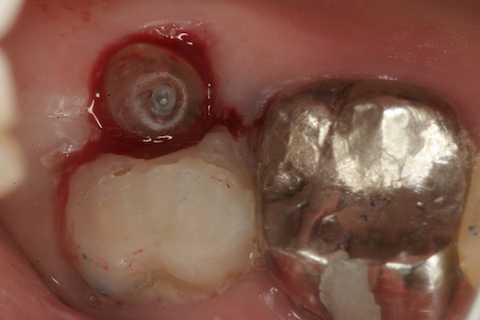

今日の抜歯再植術シリーズ35.3 2025.11.19

今日の抜歯再植術シリーズ39.3 2025.11.16

今日の抜歯再植術シリーズ39.2 2025.11.15